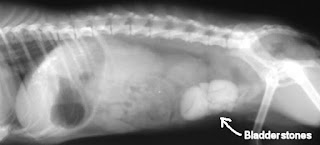

Bladder Stone / Slude ( Calculi )

| Bladder Stone in Rabbit |

Bladder stones or sludge can be diagnosed by physical examination, urine analysis or X-rays.